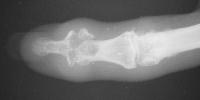

Final implant radiographs.

6 months postop.

Xrays one year out.

Progressive PIP changes remain a problem.